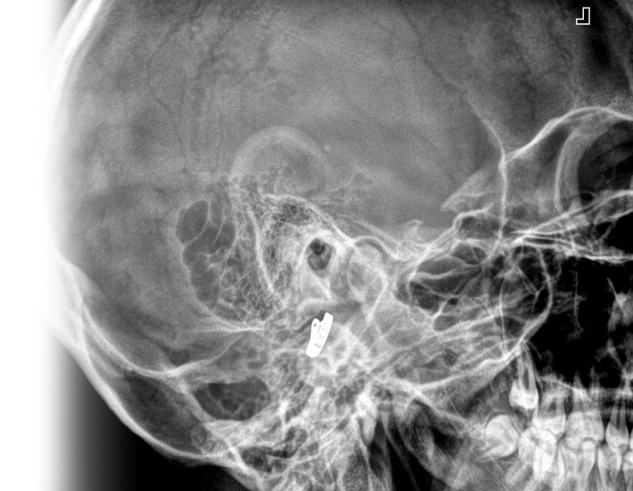

Рентгенография височных костей – важный метод прицельного исследования, который позволяет оценить структуру височных костей.

1. Рентгенография височных костей в поперечной проекции (укладка по Стенверсу)

Прицельное исследование пирамиды височной кости, ее верхушки и внутреннего слухового проход.

2. Рентгенография височных костей в косой проекции (укладка по Шюллеру)

Прицельное исследование структуры сосцевидного отростка, височно-нижнечелюстного сустава, выполняется в одной проекции.

3. Рентгенография височных костей в осевой проекции (укладка по Майеру)

Прицельное исследование среднего уха, выполняется в одной проекции.